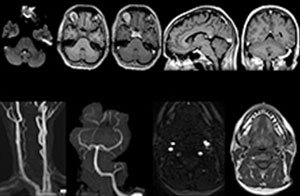

To minimize the time taken to perform scans, rapid MRI examination protocols (ExamCards) were developed, shortening the total scanning time to even less than 10 minutes in some exams. Techniques like mDIXON (modified DIXON) are used for robust capturing of fat-free MRI images in a hectic ED environment.

“We use mDIXON TSE extensively in our spine imaging in the emergency room,” says Dr. Karis. “It’s particularly nice in that it is very robust with regard to susceptibility type of problems that would come up with traditional spectral fat-saturated images; these problems are essentially eliminated with the mDIXON technique. In our ED environment it’s really nice to have the fat-free imaging that goes along with the mDIXON technique.

“For the thoracic and cervical spine routine non-contrast exam, for example, we perform one mDIXON T2 TSE sequence, which provides us with two outputs: the fat-and-water-together T2-weighted images, as well as the water-only sagittal T2-weighted images. And then we also perform an axial gradient echo exam.”

Cervical spine routine exam

This patient presented with headache that was worse with neck flexion and we see a Chiari 1 malformation with low-lying cerebellar tonsils as well as some degenerative cervical thrombolytic change.